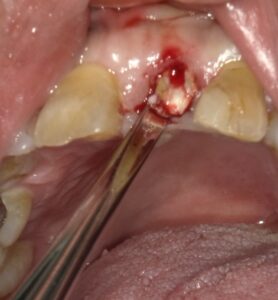

差し歯を外すと十分な根の長さがないのがわかります。抜歯を行いました。